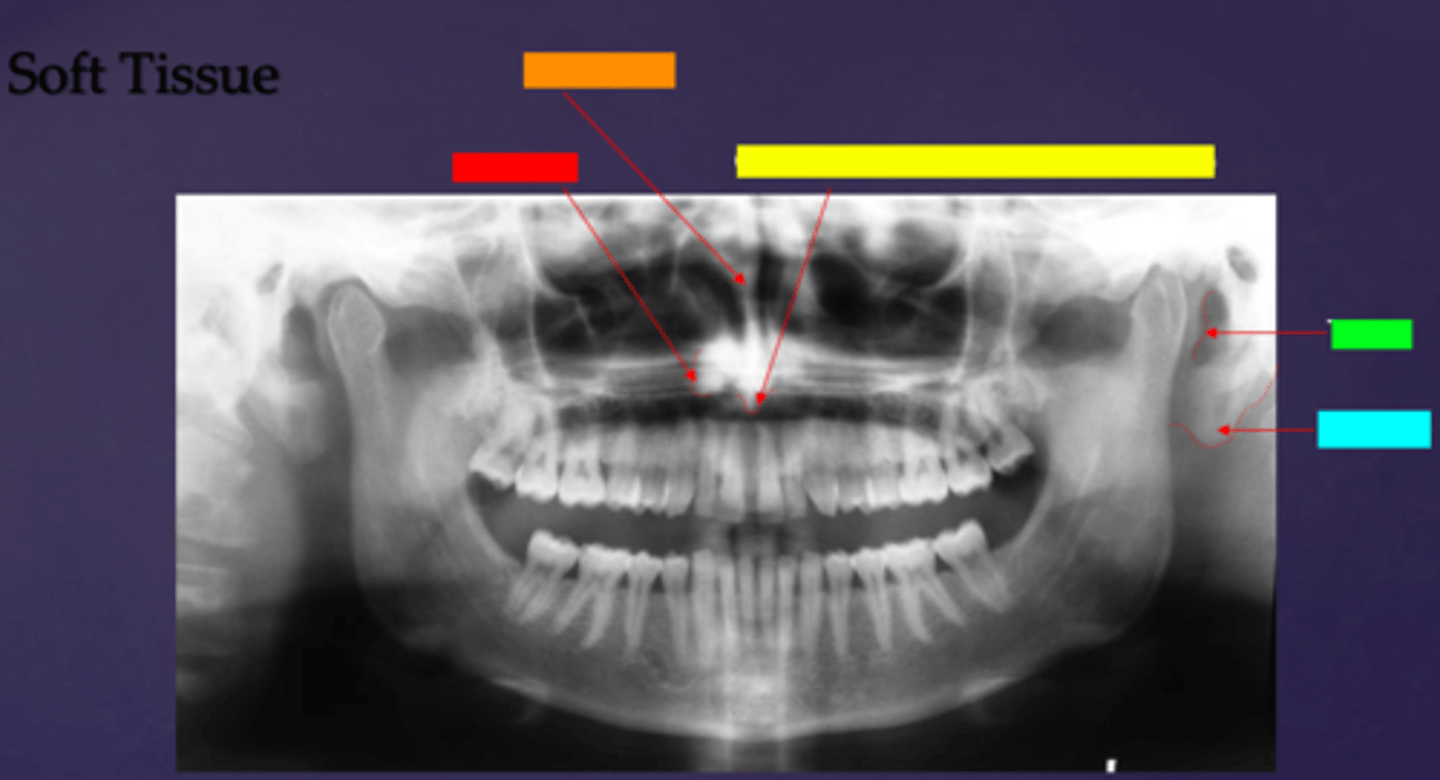

ID the soft tissue anatomy indicated by the arrow pointing from the red box:

posterior pharyngeal wall

ID the soft tissue anatomy indicated by the arrow pointing from the orange box:

soft palate

ID the soft tissue anatomy indicated by the arrow pointing from the yellow box:

dorsal surface of tongue

ID the soft tissue anatomy indicated by the arrow pointing from the green box:

middle nasal meatus

ID the soft tissue anatomy indicated by the arrow pointing from the light blue box:

inferior nasal meatus

ID the soft tissue anatomy indicated by the arrow pointing from the hot pink box:

inferior nasal concha (turbinate)

ID the soft tissue anatomy indicated by the arrow pointing from the brown box:

upper lip

ID the soft tissue anatomy indicated by the arrow pointing from the white box:

lower lip

ID the soft tissue anatomy indicated by the arrow pointing from the grey box:

ghost image of opposite mandible

ala of nose

nasal septum

columna (the septum separating the nostrils)

tragus

ear lobe